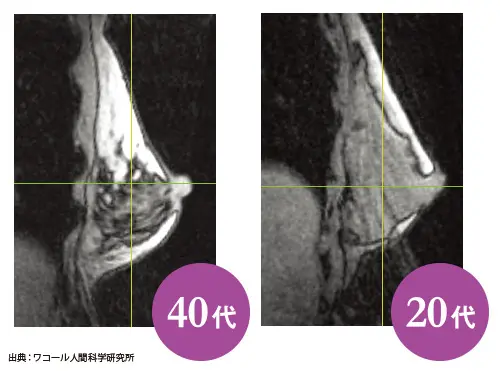

加齢によってバストの中身はこんなに変化

加齢によるホルモンバランスの変化により、乳腺と脂肪の構成比が変わる。左の写真の白く見えているのが脂肪。20代のときよりも40代のほうが白い部分が多くなっている。これによりバストが柔らかくなる。また、それを支えるクーパー靭帯も揺れなどの負担で伸びてしまう。